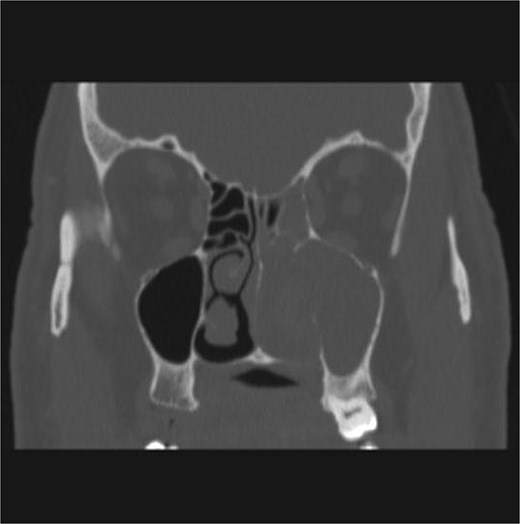

The patient underwent staging CT which was negative for distant metastasis. He then went underwent incomplete medial maxillectomy, ethmoidectomy, and sphenoidotomy followed by 10 sessions of immunotherapy abroad. He presented to our institution for follow up 6 months later with history of left nasal block and epistaxis. Nasal flexible scope showed a reddish nasal mass with greenish secretions (Fig. 3). Follow up CT revealed tumor recurrence (Figs 4 and 5). He was advised for multidisciplinary team evaluation to plan the treatment but he refused any intervention and lost follow up.

Coronal section of CT paranasal sinus bone window showing bony erosions of nasal septum, maxillary wall, lamina papyracea, and cribriform plate.